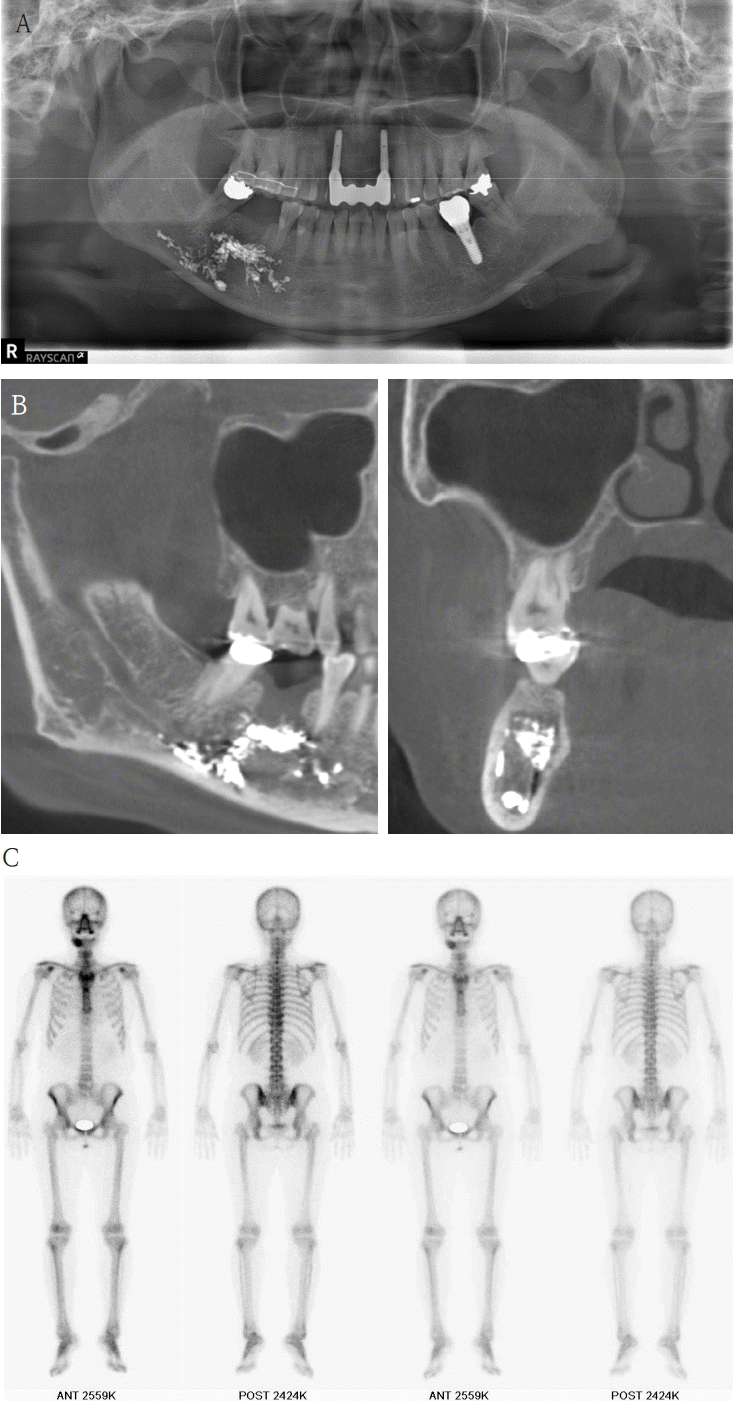

A 63-year-old female presented three days after endodontic treatment of the mandibular left second molar (#37) with symptoms of numbness in the left lower lip and gingiva. A panoramic radiograph and cone-beam computed tomography (CBCT) revealed extrusion of Calcipex II into the mandibular canal (Fig. 1). Initial neurosensory testing demonstrated mild hypoesthesia. She was admitted for foreign body removal and neurorrhaphy under general anesthesia. A post-operative panoramic radiograph confirmed the removal of the foreign body (Fig. 2). Although surgical curettage and neurorrhaphy were performed on the fourth day post-onset, no significant symptom relief was noted at the one- and two-week follow-ups. At the three-month follow-up, she reported persistent numbness with mild neuropathic discomfort but no marked improvement. A follow-up neurosensory exam is scheduled for the six-month check-up.- Case 2

A 61-year-old female presented with intermittent right mandibular swelling and pain after root canal therapy was done using EndoSeal MTA 5 months ago. A panoramic radiograph, CBCT and bone scan confirmed material extrusion and mild localized bone changes (Fig. 4). Initial neurologic evaluation demonstrated nearly normal sensory function, with Visual Analog Scale (VAS) 4 discomfort. Surgical curettage was performed under local anesthesia. A post-operative panoramic radiograph confirmed the substantial removal of the foreign body (Fig. 5). Postoperatively, the patient reported significant improvement at both the one- and two-month follow-ups. Due to full symptom resolution, no follow-up neurosensory testing was performed.- Case 4

Figure 4.

A. Pre-op panoramic radiograph of Case 3 patient. B. Pre-op CBCT of Case 3 patient. C. Pre-op bone scan of Case 3 patient